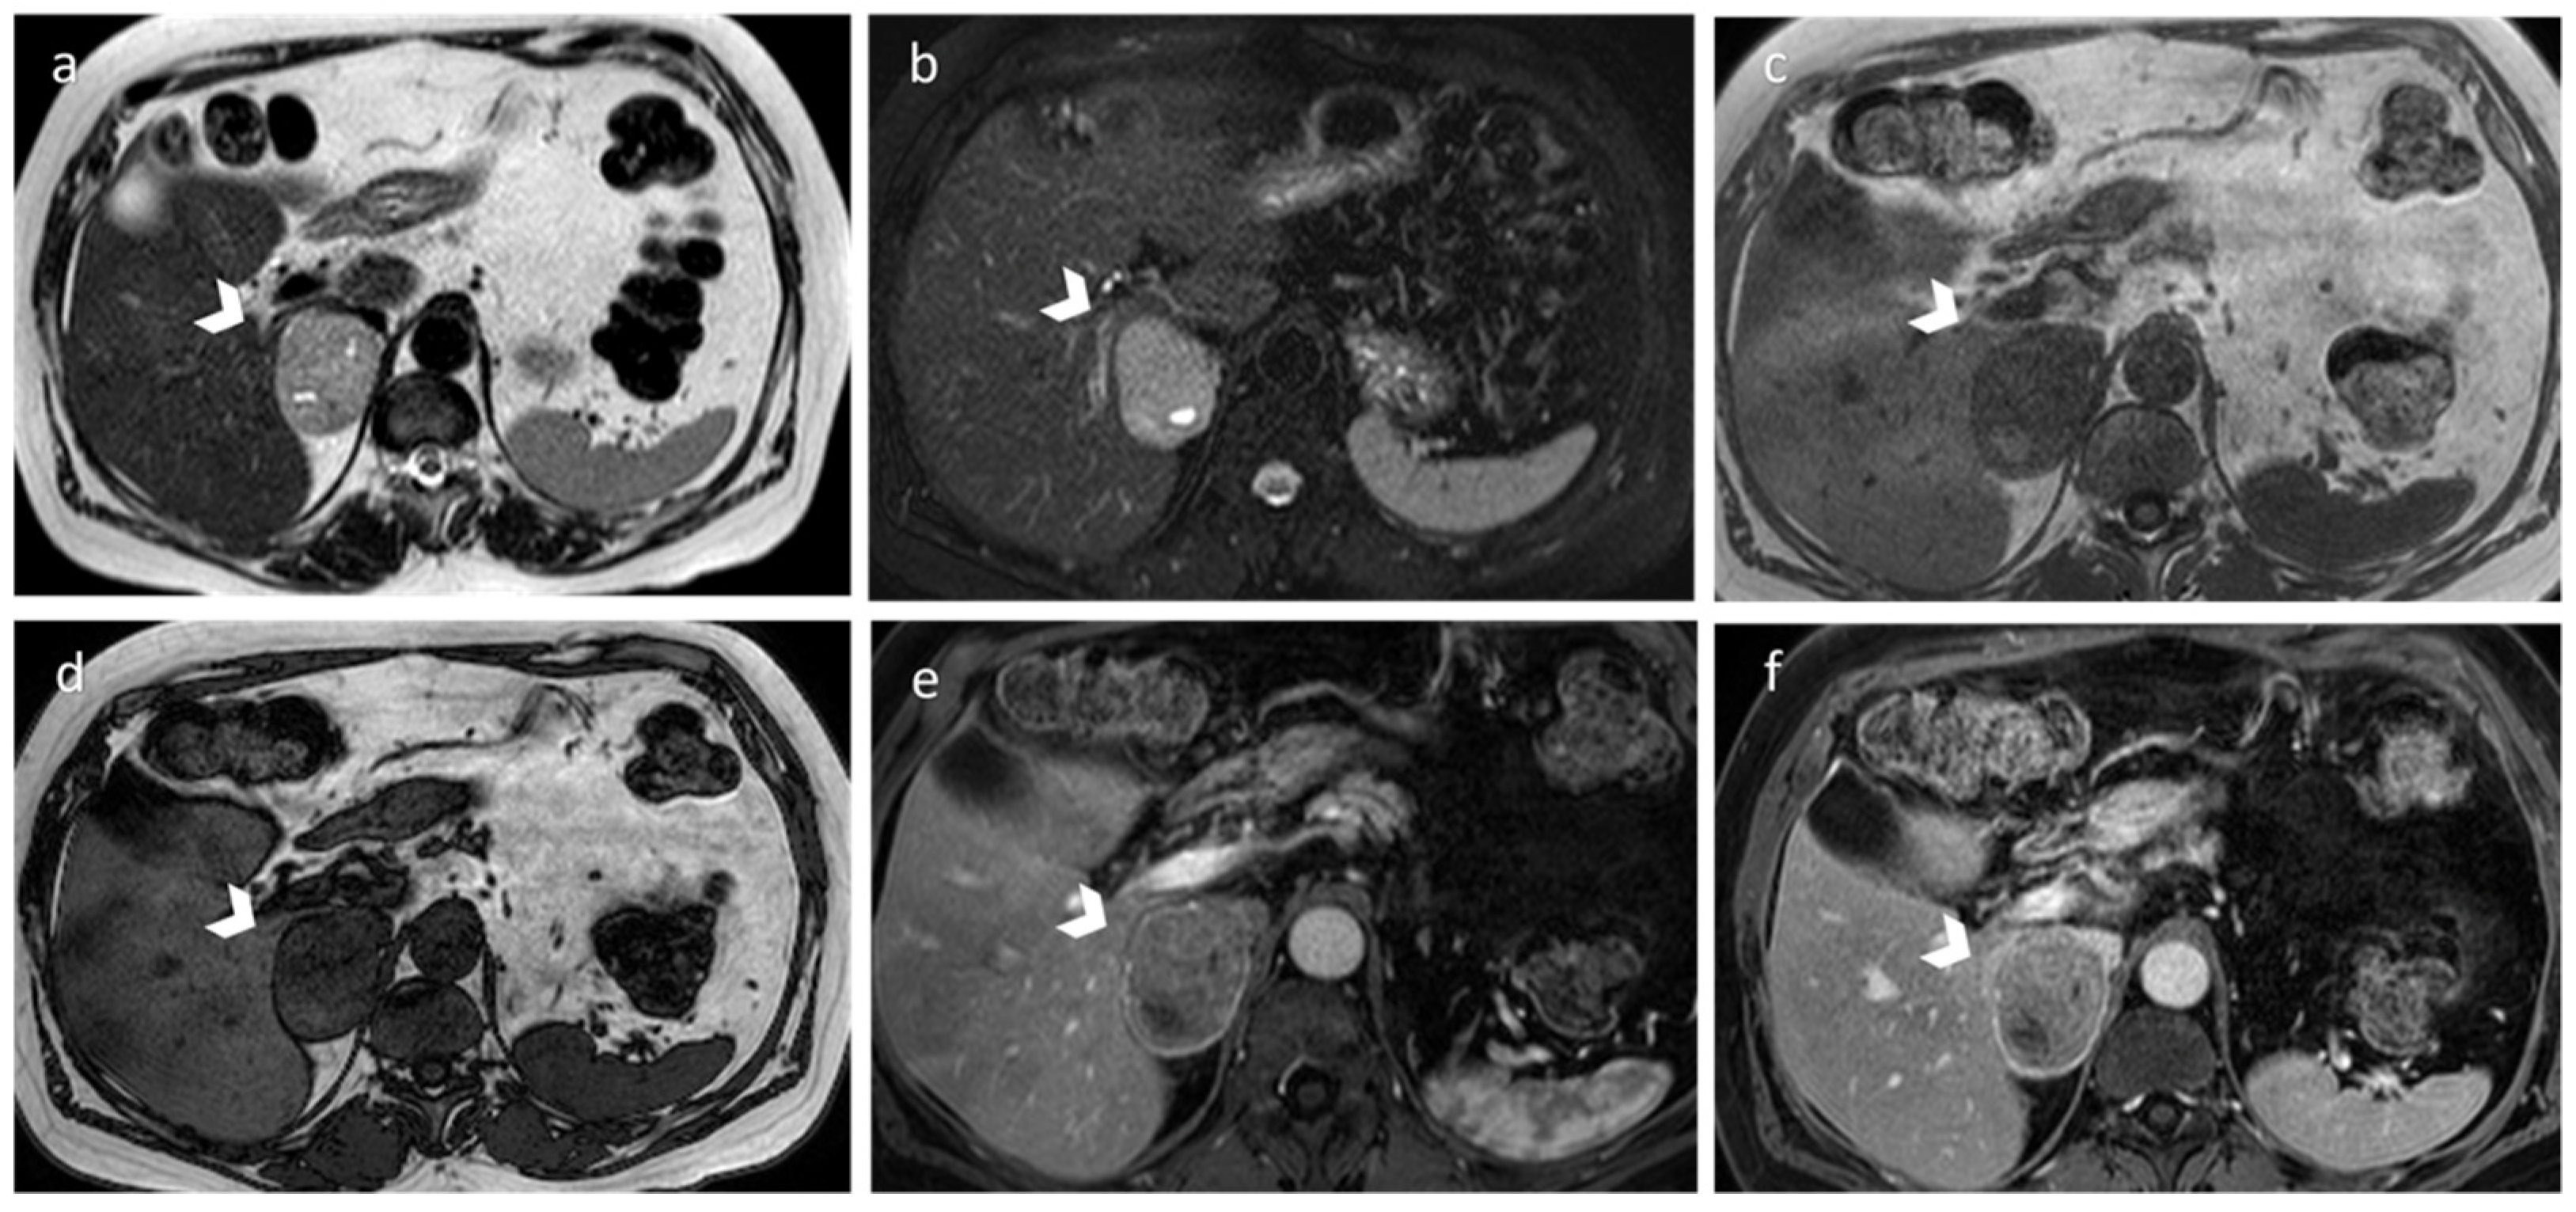

3.1. Pheochromocytoma